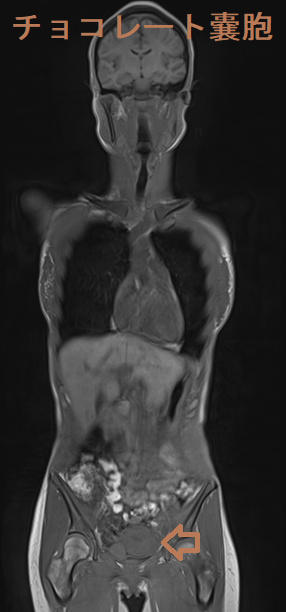

骨盤部単純MRI 画像では、背側が低信号になる(shading)。

甲状腺乳頭癌の術後にDWIBS:ドゥイブス を行った際、偶然発見されたチョコレートのう胞(卵巣子宮内膜症)、

チョコレートのう胞(卵巣子宮内膜症)は、0.7-1.6%が子宮内膜症関連卵巣癌(EAOC)に悪性転換します(Reproduction. 2004 Mar; 127(3):293-304.)。組織型は明細胞癌、類内膜癌など。チョコレートのう胞(卵巣子宮内膜症)の既往がある女性において、衣服がきつくなるなど腹部膨満感・下腹部膨隆の自覚症状がおこり、下腹部に可動性のない腫瘤を触れた場合、子宮内膜症関連卵巣癌(EAOC)が疑われます。